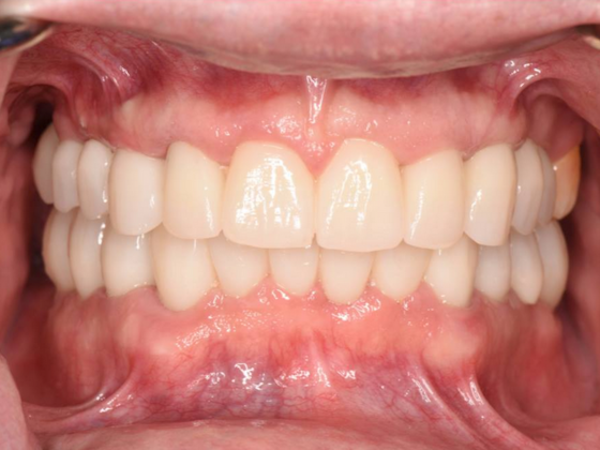

See the Difference

We Can Make

Our friendly team provides healthy smiles to patients who have endured dental trauma and oral health issues.

Dr. Jovanovski has been in practice since 2009. Since then, he has been providing patients with healthy, functional smiles, no matter how long they have forgone dental treatment. Our dentistry practice is known for taking on difficult cases and returning healthy smiles to patients who have endured dental trauma and extensive oral health issues.